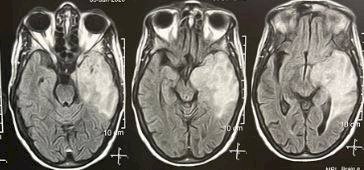

فور حضور الفريق بداية الاسبوع حضر للطوارئ مريض بالغ من العمر ٨٣ عاما يعانى من نزيف حاد بالمخ اثر ارتفاع ضغط المخ وعلى الفور تم تحضير المريض فى وقت لا يتجاوز ال ٣٠ دقيقه لدخول مباشر للعمليات لتفريغ النزيف بحرفيه شديده و نقله بعدها لتلقى العلاج والمتابعة بالرعاية المركزة و بعدها حضر شاب بالغ من العمر ١٥ عام فى حادث سير يعانى من اضطراب شديد فى درجه الوعى ناتج عن نزيف حاد خارج الام الجافية وكسور بعظام الجمجمة وعلى الفور تم ادخال المريض للعمليات لأجراء جراحه عاجله لتفريغ النزيف لإنقاذ حياه هذا الشاب.

تلاها حاله منظار مخى اخر لطفله تبلغ من العمر ٢٧ يوما بالحضانة تعانى من التهاب سحائي حاد غير مستجيب للمضادات الحيوية و صديد ببطينات المخ وقد كان المنظار المخي استكشافي و تم غسيل السائل النخاعى تماما من الصديد بواسطه المنظار المخى و اخد عينات من الصديد للتحليل وعمل مزرعة لاستكمال خطه العلاج والمتابعة بالحضانة.

ليختتم الفريق تألقه بعمل جراحه ميكروسكوبيه دقيقه لاستئصال ورم بالمخ لسيده بالغه من العمر ٥١ سنه وهى بعد الجراحة ف حاله جيده لتتلقى باقي الخطة العلاجية والمتابعة بالرعاية المركزة.

بعدها تم اجراء جراحه لاستئصال وحمة دموية نازفه بالمخيخ بواسطة الميكروسكوب الجراحى لطفله تبلغ من العمر ٩ سنوات وهى بحاله جيده لتلقى متابعه ما بعد الجراحة و استكمال خطه العلاج برعاية الاطفال.